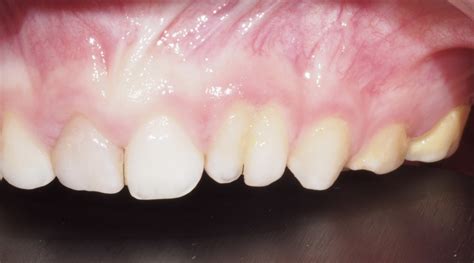

Ejemplo de dientes fusionados.